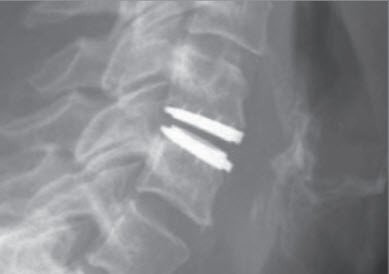

Um Form und Stabilität der Halswirbelsäule zu erhalten, wird die Bandscheibe oder der Wirbelkörper ersetzt, und zwar mit geeigneten künstlichen Implantaten, Beckenknochen oder Knochenersatz. Sie haben die Funktion eines Platzhalters anstelle der entfernten Bandscheibe oder des Wirbelkörpers. Eine Plattenfixation kann erforderlich sein, wenn es darum geht, die Stabilität der Halswirbelsäule zusätzlich zu verbessern.

Als neuere Methode kann in gewissen Fällen die Bandscheibe mit einer beweglichen Prothese ersetzt werden. Damit wird eine Versteifung vermieden, und die potenzielle Überbelastung der angrenzenden Bandscheiben und Gelenke entfällt.